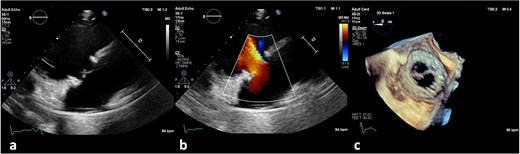

On the third day of hospitalization, transesophageal echocardiography revealed only moderate mitral regurgitation (Videos 3 and 4). However, on day 11, follow-up echocardiography showed a 7 × 18 mm vegetation on the prosthetic aortic valve, with a 5 × 7 mm floating formation (Fig. 2, Videos 5 and 6). By day 21, the vegetation had progressed, with a new formation on the tricuspid valve, an aortic annulus abscess, and worsened mitral regurgitation to severe (Figs 1 and 3, Videos 7 and 8). The development of double-sided endocarditis is very rare, and since the patient experienced it twice, congenital predisposing factors such as Patent Foramen Ovale and ventricular septal defects were ruled out. It was hypothesized that multiple predisposing factors ultimately led to the reinfection. Active IV drug use and its potential immunosuppressive effects, along with persistent poor dental condition and recurrent cutaneous infections, were identified as the main contributors, in addition to the patient’s overall non-adherence, for the development of double-sided endocarditis on two occasions.

(a) No vegetation, valve destruction of the prosthetic tricuspid valve on TTE RV inflow view, (b) No PVL of the prosthetic TV (TTE color doppler), (c) no signs of prosthetic IE on TV in TEE (day 21 of hospitalization).